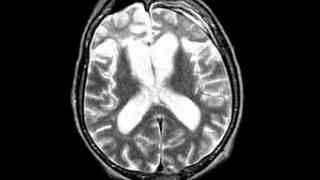

Cerebrovascular Disease Multiple embolic infarction, diffusion and FLAIR imaging